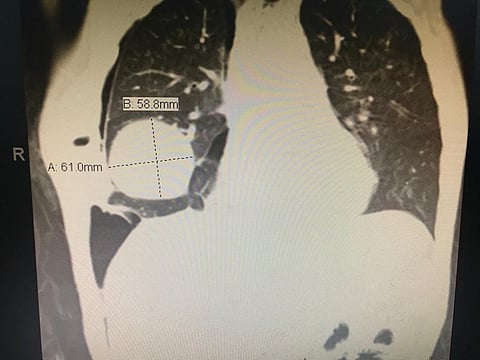

وذكر الطبيب المعالج خالد البحيري أن العملية كانت معقدة خاصة وأن الورم بالقرب من القلب والأوردة الرئوية، حيث يتطلب إجراء العملية خبرة وكفاءة عالية، وأجهزة وأدوات خاصة.